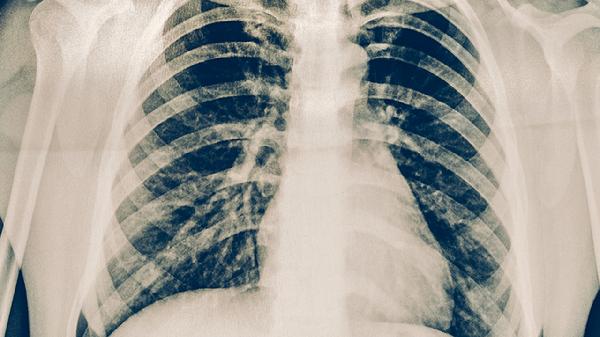

病毒性慢性肺炎患者需建立长期随访计划,每3-6个月复查胸部CT。每日进行腹式呼吸和缩唇呼吸训练,循序渐进增加散步等有氧运动。保持居住环境湿度在40%-60%,使用空气净化器减少粉尘刺激。心理疏导有助于缓解焦虑情绪,可参加呼吸康复训练营改善生活质量。出现发热、咳痰增多等症状时及时就医。